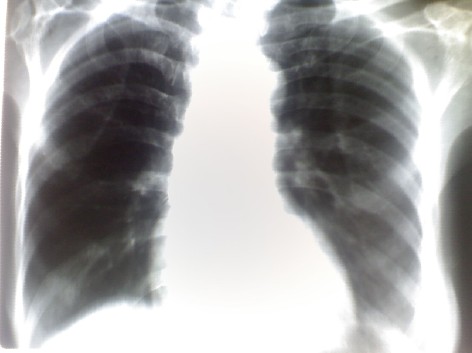

患者,女性,68岁,之前行ct检查示:有肺部感染

右肺透光度增加

左膈都不见了,片子所示的部分未见明显肺实质性病变。

只知道是胸片,看不出有感染。

左侧膈肌未包括。属不合格片。既然有ct,为什么不上传ct呢?此片太白,看不到实质性病变。再者,ct与此片间隔多长时间,治疗情况如何,不得而知

片子条件太差了  还是lz照相技术不好啊  感觉左侧膈面和肋膈角都没显示完全